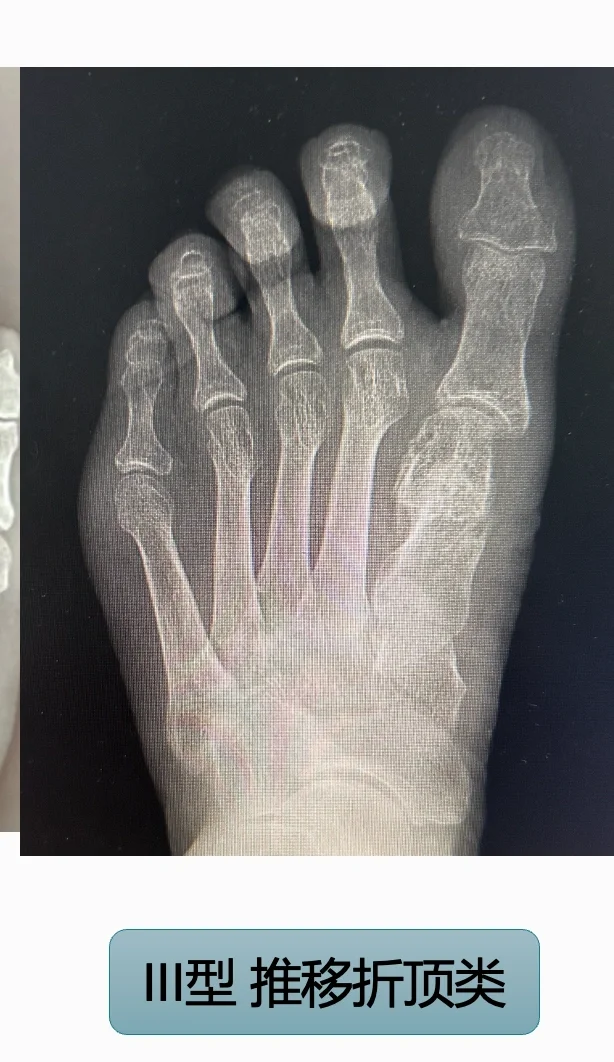

III型:短缩推移,然后靠夹卷内翻,用趾骨推挤跖骨头保持矫形效果。这种容易出现二趾的转移跖骨痛,如果拇趾下不硌脚一般不用翻修,缩短二趾调整横弓即可。如果症状明显,翻修也很困难,难点主要在肌腱挛缩后无法再延长拇趾。

拇趾不能很好受力,那么负重行走的力量会分担到其他趾,那么很容易出现顽固严重的横弓塌陷和转移跖骨痛。